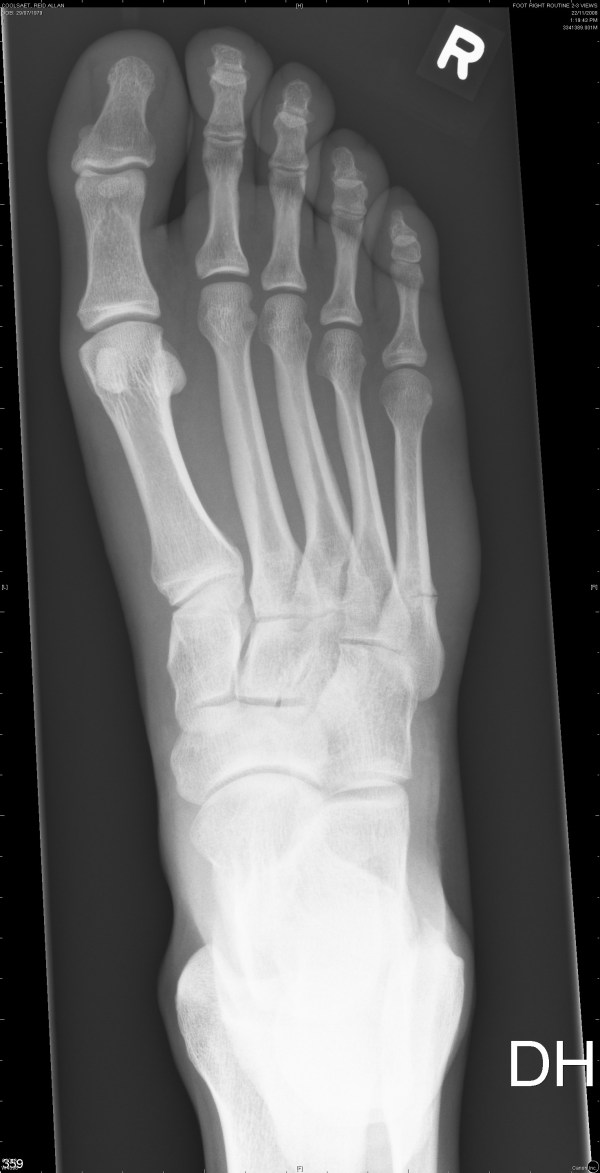

The first two are from November 6th and the last two are from November 22nd.

The fifth metatarsal (long bone on the far right) is broken.